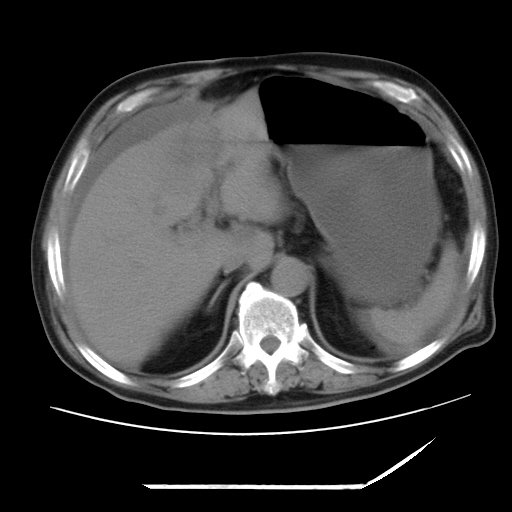

以下是引用zxl51642在2009-8-12 18:55:00的发言:[br]1、肠系膜脂肪浑浊,密度增高,腹水,支持腹膜炎诊断;2、右肾盂及输尿管中段结石,左输尿管起始段结石;3、胆囊切除术后改变?4、双侧胸膜腔少量积液;5、胰腺体积不大,勾勒清楚,肾前筋膜无增厚,不支持胰腺炎,请结合血尿淀粉酶及临床。